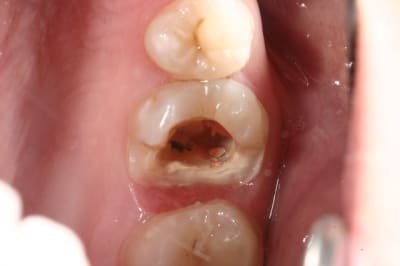

pour répondre à la question initiale du post, un cas de molaire dépulpée non couronnée.

Mise en place d'un cvimar (fuji II lc) en recouvrement de l'entrée canalaire puis onlay Empress collé.

Patiente de 21 ans.